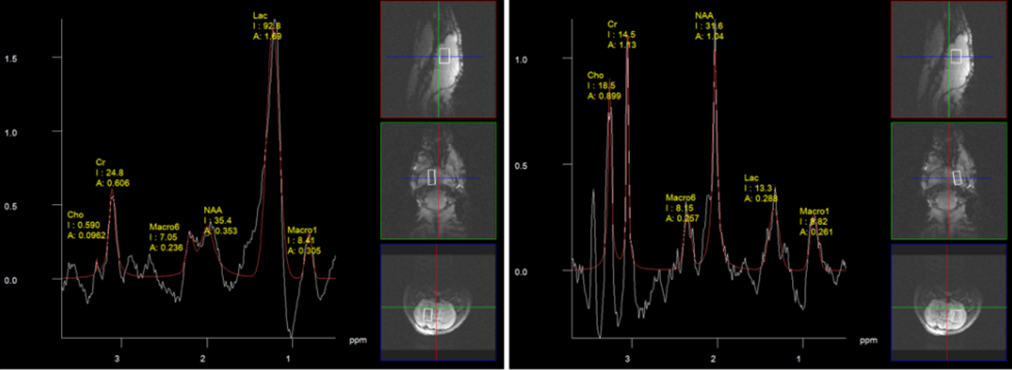

MR-Spektroskopie in Läsion (links unten) und gesundem Referenz-geweben (rechts unten) mit charakteristischen Metaboliten-Veränderungen.